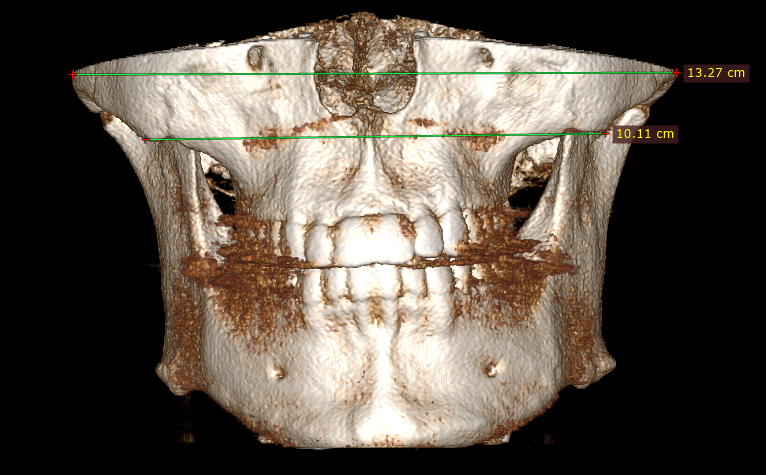

Can't even mew properly or breath effectively by the nose (compressed airways and 32.5mm palate).

- MARPE distraction (mini-screw expander) with microperforations under local anesthesia (min. 7mm expansion);

However I am concerned with how it would look since they are mainly focused on functional expansion and not so much aesthetic, they said they would expand mainly in the anterior palate and not so much in the posterior.

Can't even mew properly or breath effectively by the nose (compressed airways and 32.5mm palate).

- MARPE distraction (mini-screw expander) with microperforations under local anesthesia (min. 7mm expansion);

However I am concerned with how it would look since they are mainly focused on functional expansion and not so much aesthetic, they said they would expand mainly in the anterior palate and not so much in the posterior.